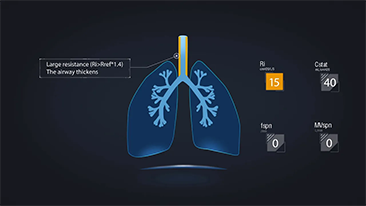

A escolha das configura??es corretas do respirador para o tratamento de pacientes com doen?as do trato respiratĂłrio Ă© uma quest?o muito importante. Como a tarefa de especificar os par?metros do equipamento de ventila??o Ă© inteiramente realizada por um mĂ©dico, o conhecimento e a experiĂȘncia do mĂ©dico na sele??o desses par?metros tem um efeito direto na precis?o de suas decis?es. O paradigma do atendimento de apoio aos pacientes mudou significativamente ao longo dos Ășltimos 20 anos. Atualmente, vĂĄrios modos de ventila??o e ferramentas de apoio Ă decis?o foram desenvolvidos em torno das necessidades clĂnicas para ajudar os profissionais clĂnicos a melhorar a eficiĂȘncia e eliminar os erros nas decis?es clĂnicas.

Integrando oxigenoterapia de alto fluxo, ventila??o n?o invasiva e ventila??o invasiva, os respiradores 3 em 1 da sĂ©rie SV reĂșnem desempenho estĂĄvel, fun??es versĂĄteis e facilidade de uso. Os recursos excepcionais de prote??o pulmonar e as vĂĄrias ferramentas de apoio Ă tomada de decis?es dos respiradores s?o projetados para diminuir o risco de infec??es cruzadas e facilitar a rotina diĂĄria dos profissionais clĂnicos.